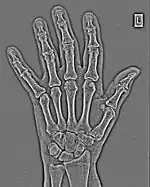

The essence of this approach is that it can be used to produce a range of image processing effects by enhancing and/or suppressing features in the 2D-FFT and then converting the result back into the spatial domain using the IFT, as illustrated in Figure 1.28. Such image manipulations are considered in more detail in a later chapter. Note that the form of image processing demonstrated in the figure is for purely illustrative purposes and bears no direct medical significance.

![]() Fig. 1.28(a): A radiograph of the wrist. | ![]() Fig. 1.28(b): The wrist radiograph processed by attenuating periodic structures of size between 1 and 10 pixels. |

![]() Fig. 1.28(c): The wrist radiograph processed by attenuating periodic structures of size between 5 and 20 pixels. | ![]() Fig. 1.28(d): The wrist radiograph processed by attenuating periodic structures of size between 20 and 50 pixels. |